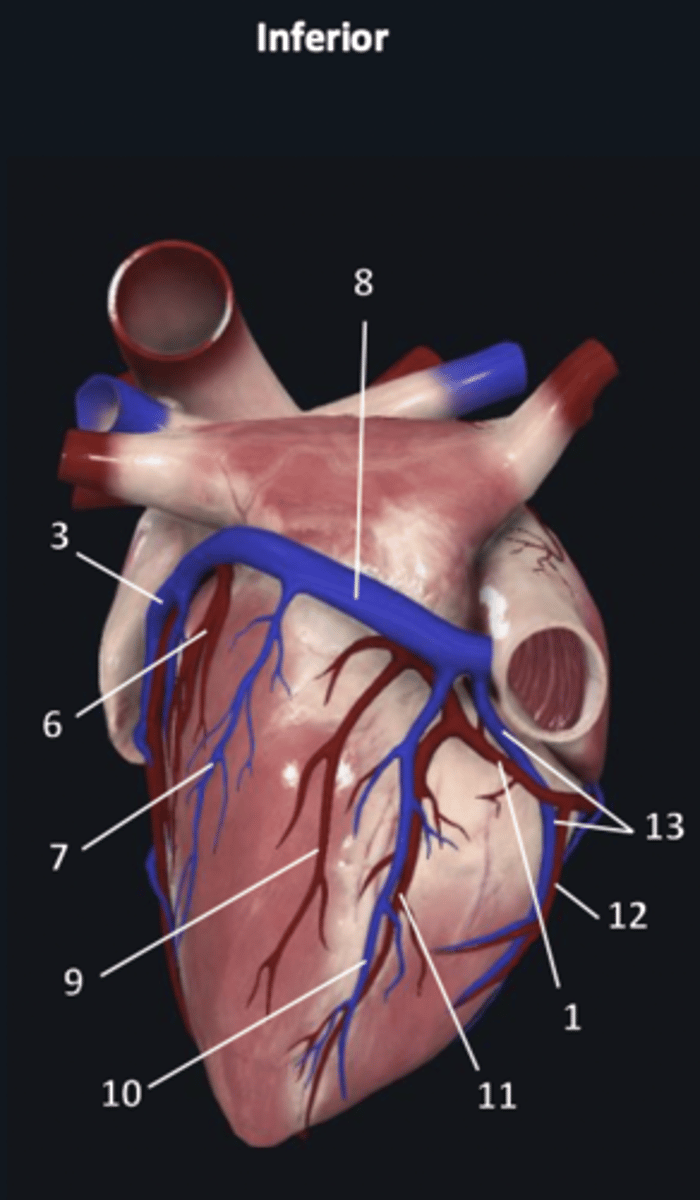

right coronary artery

1

anterior interventricular artery

2 (red)

great cardiac vein

3 (blue)

anterior interventricular artery

2 (red)

great cardiac vein

3 (blue)

left marginal artery

4

left marginal vein

5

posterior left ventricular artery

6

posterior vein of left ventricle

7

coronary sinus

8

right coronary artery

1 (red)

great cardiac vein

3

posterior left ventricular artery

6

posterior vein of left ventricle

7

coronary sinus

8

right posterolateral artery

9

middle cardiac vein

10

posterior interventricular artery

11

right marginal artery

12

small cardiac vein

13